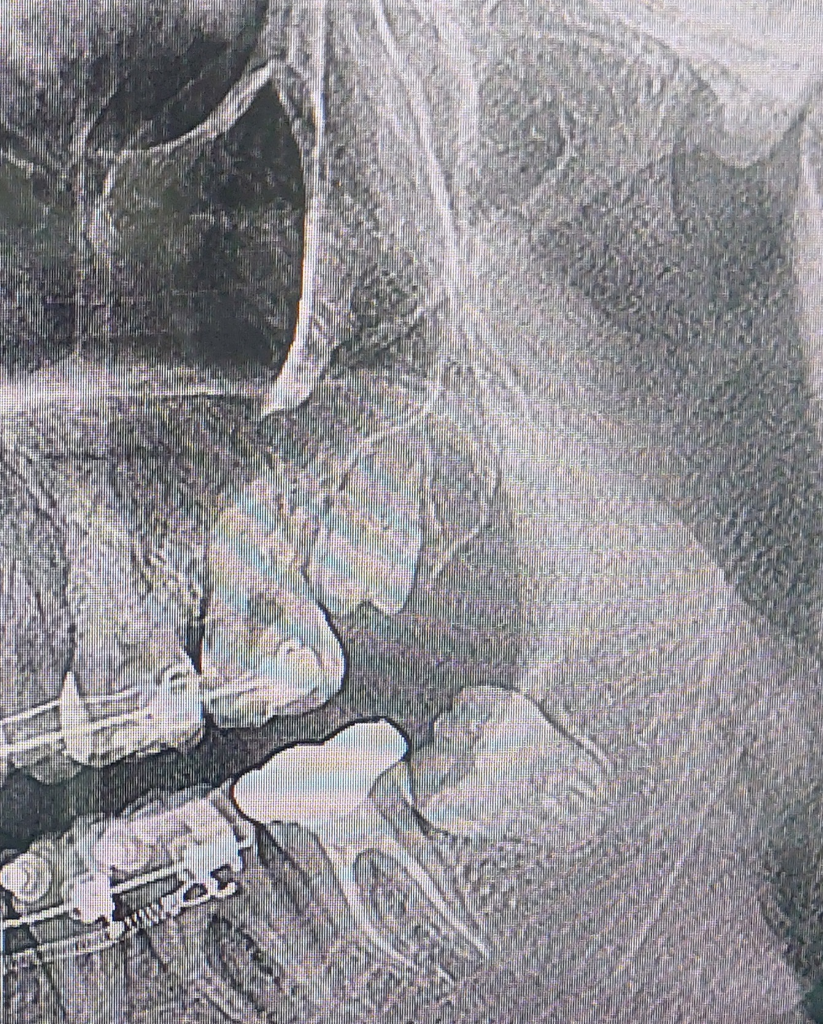

사랑니가 매복인지 아닌지 궁금합니다

사랑니가 3개인데 오른쪽 아래 사랑니 먼저 뽑으라고 해서 뽑기는 할건데, 엑스레이 사진 보니까 궁금한게 생겨서 질문드립니더. 보시다시피 왼쪽에 사랑니가 두개잖어요? 하악의 사랑니는 반매복인데 그 위에 상악 사랑니는 매복인가요 아니면 잇몸 맹출된 사랑니인가요? 교정장치 때문에 손으로 만져봐도 잘 모르겠어요. 상악의 사랑니가 가장 뽑기 쉽다고 하던데요..

상악에 있는 사랑니는 치조골과 잇몸 라인을 보았을 때는 완전히 매복되어 있습니다. 다만 교정을 하면서 해당 치아가 점점 위로 맹출할 가능성도 있어 보입니다. 지금 상태에서는 바로 발치하더라도 큰 무리는 없어 보입니다. 하악 사랑니 보다 난이도가 높지 않습니다.

윗쪽 사랑니는 완전 매복된 사랑니 입니다. 경사져 매복된 사랑니로 윗쪽 매복사랑니가 더 뽑기 어려운 경우가 많이 있으며 지금 케이스도

윗쪽 사랑니 뺄려면 고난도의 수술이 필요해 보입니다.

위쪽 사랑니도 매복사랑니 같습니다. 하지만, 뼈속에 잇는건 아니고 잇몸안에 잇는상태인거 같습니다. 크게 어려운 발치는 아닌거 같습니다.